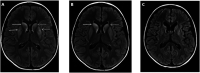

Primary carnitine deficiency (PCD) is caused by pathogenic variants of the SLC22A5 gene, which encodes a transmembrane protein that functions as a high affinity carnitine transporter. Carnitine is essential for the transport of acyl-CoA, produced from fatty acids, into the mitochondria where they are oxidised to produce energy. We present the case history of an 8-year-old boy who presented with fever, lethargy, focal rhythmic (3 Hz) left wrist twitching, and severe encephalopathy. MRI brain showed basal ganglia involvement. Metabolic investigations revealed low serum carnitine; whole genome sequencing confirmed compound heterozygous SLC22A5 mutations. With carnitine replacement, intensive care support, and neurorehabilitation, he made a remarkable recovery, regaining independent breathing, speech, mobility, and hand use. Seizure presentation in PCD is rare and presentation with sustained focal myoclonus has not been previously reported. This case expands the known phenotype of PCD. Prompt carnitine replacement is imperative.